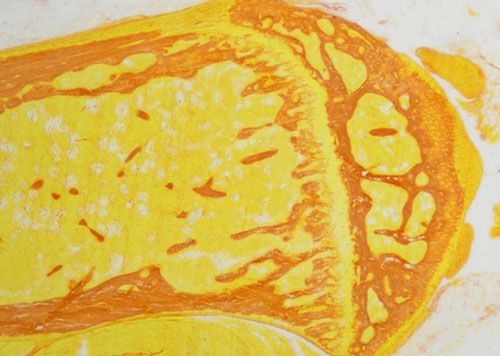

天狼猩紅和KWS都是強酸性染料,易與膠原分子中的堿性基團結合,吸附牢固。偏振光鏡檢查,膠原纖維有正的單軸雙折射光的屬性,與KWS-天狼猩紅結合,可增強雙折射,提高分辨率,從而區分兩型膠原纖維。未脫鈣骨組織切片經天狼猩紅染色后,普通光學顯微鏡下,膠原纖維呈紅色或鮮紅色,其他呈黃色;在偏振光顯微鏡下,Ⅰ型膠原纖維呈強橙黃色或亮紅色,Ⅲ型膠原纖維呈綠色。

未脫鈣骨天狼猩紅染色